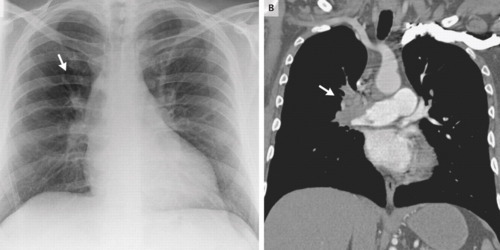

Qual o nome do sinal da primeira figura?

O que indica?

Sinal de WESTERMAK

(oligoemia - hipertransparência - localizada)

Resultado da obstrução ao fluxo sanguíneo naquela região - TEP

Qual o nome deste sinal?

O que significa?

Sinal de HAMPTON

Área de hipotransparência em cunha - local do infarto pulmonar - TEP

Sinal de PALLA

Dilatação do ramo descendente da artéria pulmonar